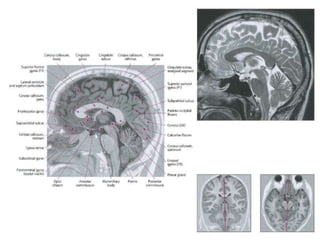

• The tectum (“roof”) is the dorsal part of the

mesencephalon (midbrain).

• Consists of the inferior and the superior colliculi.

– The superior colliculus is involved in preliminary visual

processing and control of eye movements.

– The inferior colliculus is involved in auditory

processing. It receives input from various brain stem

nuclei and projects to the medial geniculate nucleus

of the thalamus, which relays auditory information to

the primary auditory cortex.

– Both colliculi also have descending projections to the

paramedian pontine reticular formation and spinal

cord.

– Collectively the colliculi are referred to as the corpora

quadrigemina.

• The tegmentum (from Latin for "covering”) is

a general area within the brainstem. It is

located between the ventricular system and

distinctive basal or ventral structures at each

level.

• The midbrain tegmentum is the part of the

midbrain extending from the substantia nigra

to the cerebral aqueduct in a horizontal

section

• The nuclei of CN III and IV are located in the

tegmentum portion of the midbrain.